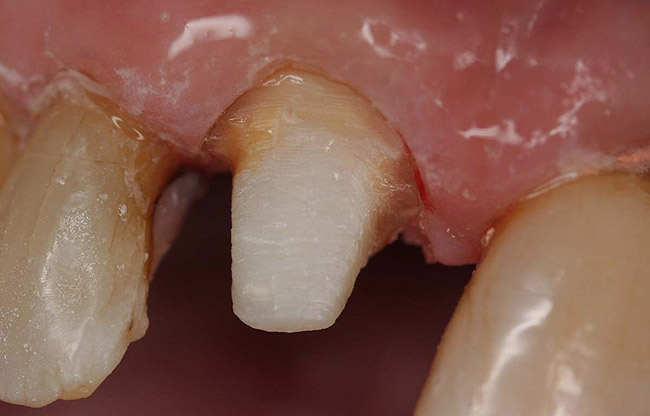

Case 1

A Class IN maxillary bicuspid was previously restored with a fiber post and an all-porcelain crown (Figure 1). The forces of the oral environment resulted in fracture of the fiber post and crown failure. The remaining fiber post in the root was removed, and anti-rotational areas were prepared for a cast post (Figure 2). A gold cast post was constructed at a dental laboratory, using an indirect technique (Figure 3). A porcelain-fused-to-metal (PFM) crown was constructed with a bevel finish to provide a ferrule and reduce forces on the post (Figure 4 and Figure 5).

Figure 3  Cast post to restore the second bicuspid.

Figure 3

Figure 4  The cast post was cemented.

Figure 4

Figure 5  The final crown.

Figure 5